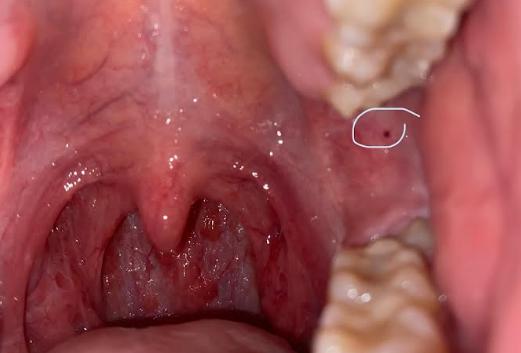

Dạ chào AloBacsi ạ. Mấy ngày nay em bị đau họng với môi bỗng nhiên bị tróc vảy khô như bị chàm. Bác sĩ xem dùm trong họng em tự nhiên có nổi cục như nốt ruồi mà trước đây em kiểm tra thì không có ạ. Môi của em bị vậy thì có cần đi tầm soát ung thư không ạ? Em cảm ơn.

Theo như hình ảnh bạn gửi ở vùng họng miệng cho thấy bạn đang có tình trạng viêm họng cấp bởi vì sự sưng nề của các cấu trúc lympho hầu họng. Khi viêm cấp những cấu trúc mạch máu dưới niêm mạc sẽ có hiện tượng tăng sinh, đôi khi có đốm xuất huyết nhỏ như bạn đã thấy trên hình là điều hoàn toàn bình thường. Bạn hãy đến bệnh viện tai mũi họng để được bác sĩ trực tiếp thăm khám và kê toa kháng sinh điều trị cho bạn nhé. Các cấu trúc này không phải là tổn thương ác tính nên bạn không cần phải quá lo lắng.

Vết tróc da ở vùng môi của bạn có thể do khô môi, Herpes hoặc giai đoạn đầu của zona, trong lúc thăm khám vùng họng miệng bác sĩ chuyên khoa cũng có thể kiểm tra vấn đề này cho bạn.

Nói chung, tình trạng bạn đang gặp phải là tổn thương cấp và có thể điều trị khỏi hoàn toàn nên bạn đừng quá lo lắng nhé.